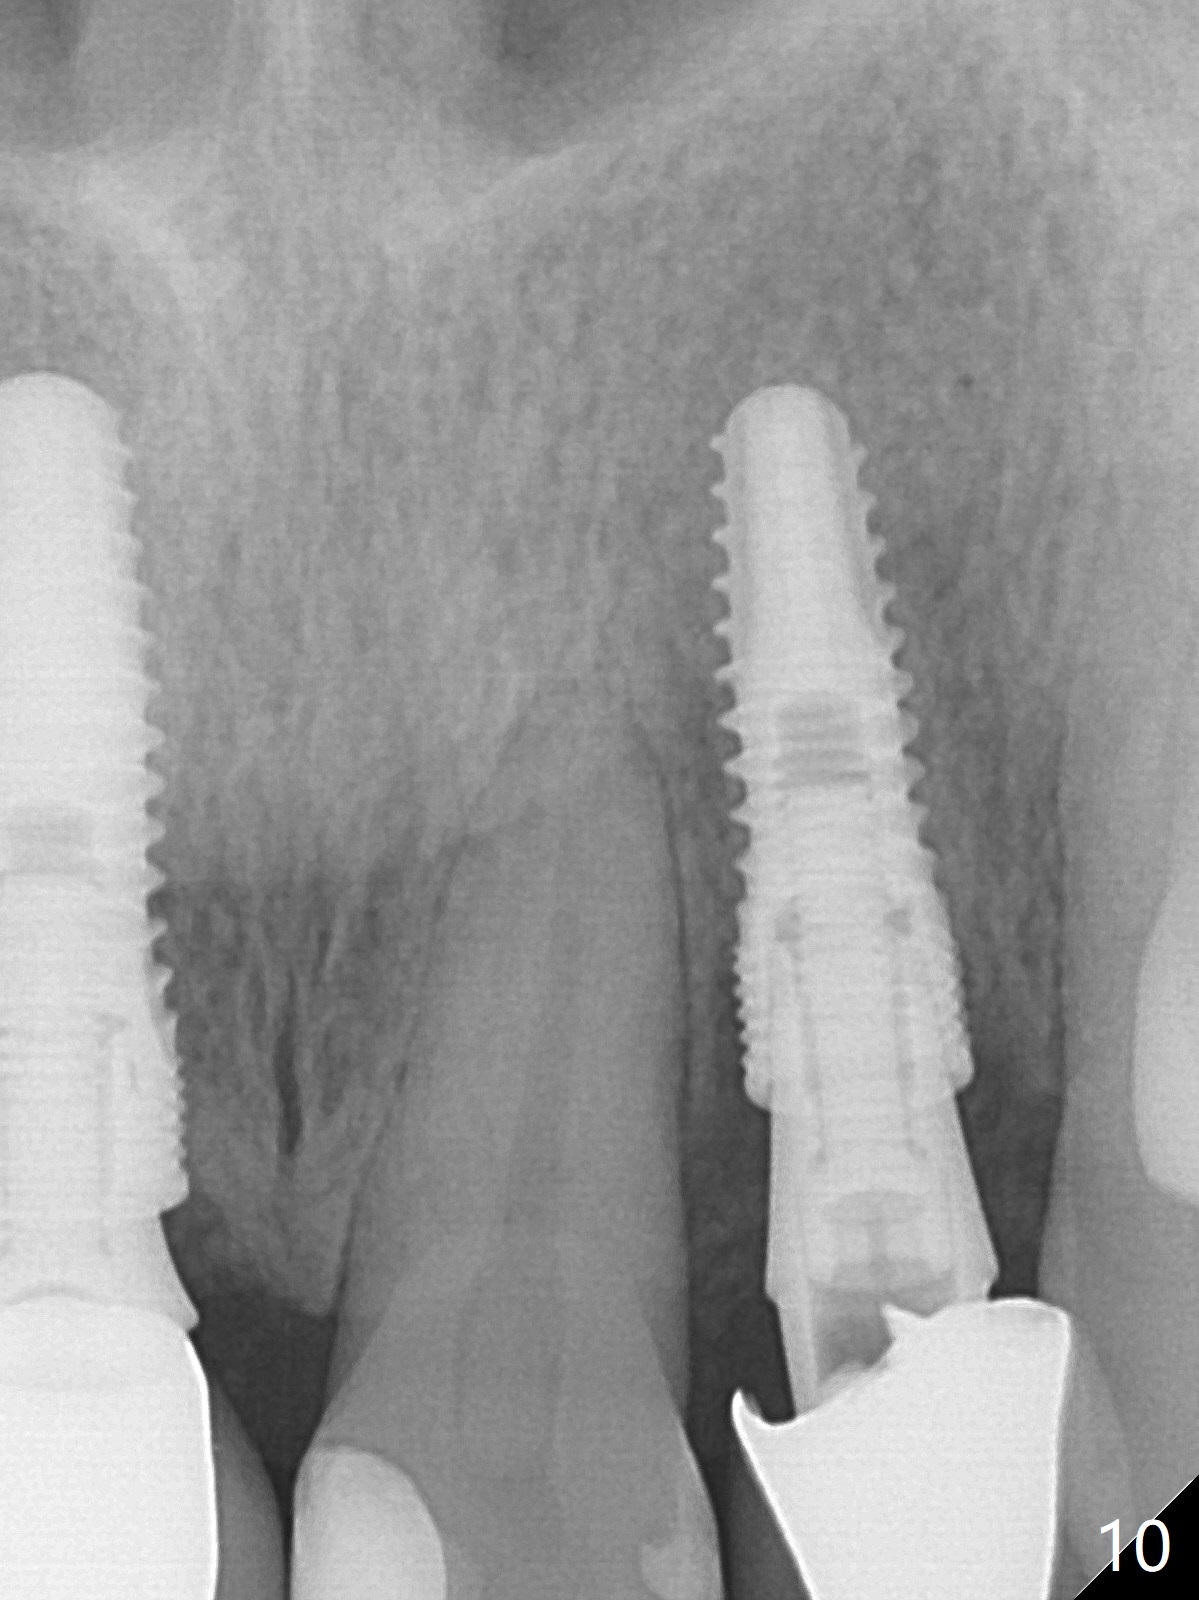

When the patient returns, the crown at #10 has displaced incisally (Fig.1,2 arrow). The initial depth is 15 mm (Fig.3, palatal gingival margin). After a 3.8x12 mm SM implant is placed (Fig.4), allograft is packed in the peri-implant space (*, as compared to Fig.3) and a 3.9x4(3) mm abutment is placed (A). More allograft is placed in the peri-abutment space (Fig.6 *). The existing crown (Fig.4,5 C) is hollowed, relined (R) and used as an immediate provisional (Fig.7-9). The patient is pleased with the appearance of the apically-repositioned provisional (Fig.7 arrow). She returns for impression 3.5 months postop (Fig.10). After change of abutment to 3.9x4(4.5) mm and new provisional, impression is retaken 5 months postop (Fig.11,12). It appears that the implant is palatally placed and a little large for the site (Fig.11 (B: buccal); Fig.12 (^: thin layer of the palatal plate)). If an angled abutment were used, a screw-retained crown might have been feasible. Due to the new provisional, the gingiva looks healthy when a permanent crown is cemented (Fig.13).